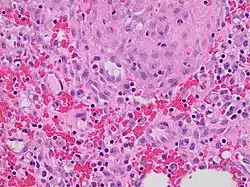

Granulation tissue is new connective tissue and microscopic blood vessels that form on the surfaces of a wound during the healing process.[1] Granulation tissue typically grows from the base of a wound and is able to fill wounds of almost any size. Examples of granulation tissue can be seen in pyogenic granulomas and pulp polyps. Its histological appearance is characterized by proliferation of fibroblasts and thin-walled, delicate capillaries (angiogenesis), and infiltrated inflammatory cells in a loose extracellular matrix.

Granulation tissue is composed of tissue matrix supporting a variety of cell types,[3] most of which can be associated with one of the following functions:

Immunity

The main immune cells active in the tissue are macrophages and neutrophils, although other leukocytes are also present.[6] These work to phagocytize old or damaged tissue, and protect the healing tissue from pathogenic infection. This is necessary both to aid the healing process and to protect against invading pathogens, as the wound often does not have an effective skin barrier to act as a first line of defense.

It is necessary for a network of blood vessels to be established as soon as possible to provide the growing tissue with nutrients, to take away cellular wastes, and transport new leukocytes to the area. Fibroblasts, the main cells that deposit granulation tissue, depend on oxygen to proliferate and lay down the new extracellular matrix.[7]

In vascularisation, also called angiogenesis, endothelial cells quickly grow into the tissue from older, intact blood vessels.[8] These branch out in a systematic way, forming anastomoses with other vessels.